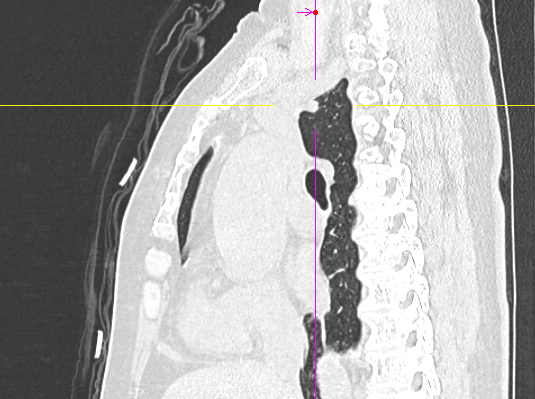

数月前,66岁的龚女士在肺癌术后随访复查中,胸部CT报告显示其右上肺新发实性结节一枚,并由刚开始发现时的5mm逐步增大至10mm。更棘手的是,这个结节位于右肺上叶尖段的纵隔胸膜下,位置极其刁钻。面对这份报告,患者龚女士陷入了深深的焦虑。因为其7年前因右中肺肿瘤行右中肺癌根治术,对于新发的实性结节为何种性质,是新发肺恶性肿瘤或是良性病变,亦或是原肺癌复发转移,目前均不能明确。辗转多家医院,得到的建议多为定期观察,等待变化或考虑创伤较大的传统穿刺活检,但结节位置非常深,单纯CT引导下定位穿刺很难精准到达,且需穿行的肺组织较多,创伤较大。

胸外科马海涛主任团队对龚女士的病情进行了深入细致的评估:结节虽小,但形态学特征具有风险,且结节逐步增大,结合既往肺癌病史,考虑肿瘤复发可能,“定期观察”方案会让患者持续承受心理煎熬。然而,传统的CT引导下经皮肺穿刺定位,对于如此深部、微小的结节,极易导致气胸、出血等并发症,风险极高。

马主任解释系统原理:“这套系统就像为我们医生的操作装上了‘肺部GPS’。它通过术前将患者的CT影像数据导入系统,构建出独一无二的肺部三维地图。术中,在磁场的引导下,我们操控一根细如发丝的导航探头,经由患者的口腔、气管这一自然通道,毫无创伤地直达常规支气管镜无法到达的肺外周深处,精准地停靠在目标结节旁边。磁导航支气管镜的优势是决定性的。它实现了‘经自然腔道、无创抵达’,彻底避免了经皮穿刺可能引起的高达20%-30%的气胸风险,为定位深部结节提供了安全、精准的解决方案。